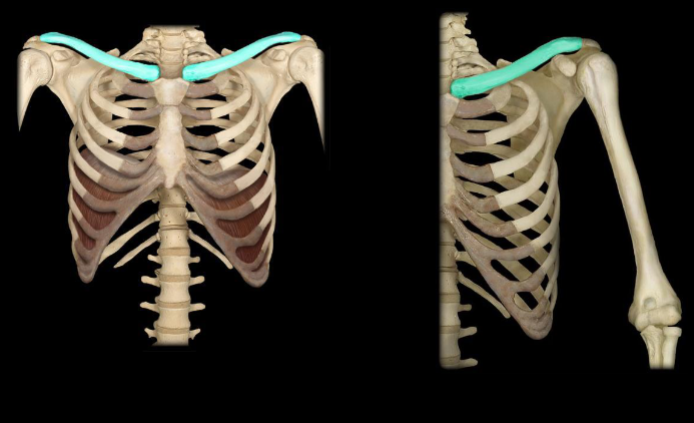

what bone is highlighted in this image?

clavicle

what is the layman’s term for clavicle?

collarbone